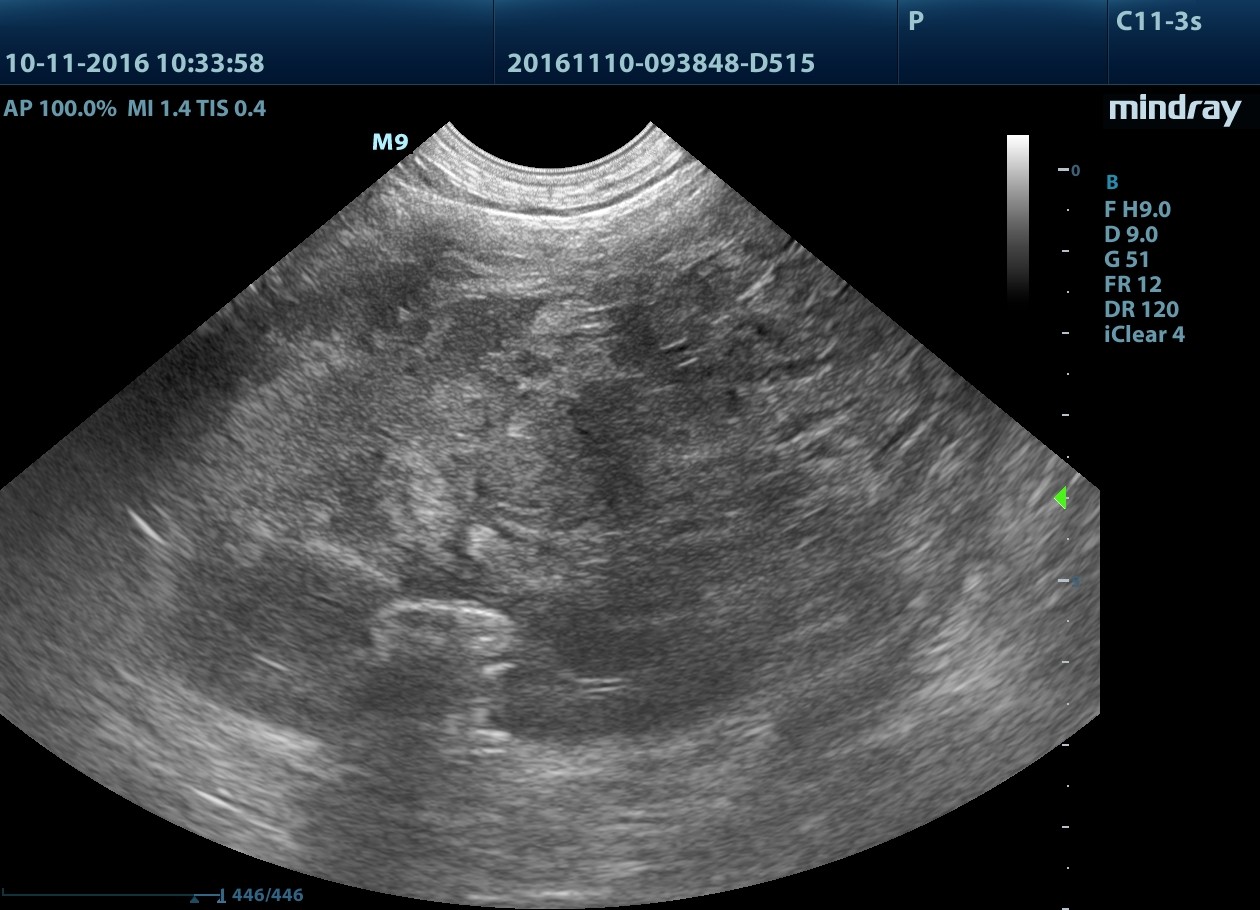

Okolicznie do lewej nerki obecność dużej, ok. 10-11 cm, owalnej struktury, heteroechogennej, w obrazie jak litej, jednak bez uchwytnego przepływu krwi (zdarza się, że nie wyłapujemy w badaniu dopplerowskim przepływu w drobnych, poskręcanych naczyniach, więc brak widocznego przepływu nie musi oznaczać braku unaczynienia zmiany).

Po dokładnym przeskanowaniu zmiany w różnych przekrojach wyraźnie widać, że jej pochodzenie jest nerkowe, obraz sugeruje duży guz nerki. Na niebiesko zaznaczona nieznacznie, do ok. 3 mm poszerzona miedniczka nerkowa, patrz: film i zdjęcie 2.

Nieco zastanawiający jest kolejny skan, na którym nerka ma całościowy, prawidłowy zarys, a wydaje się, że 10 cm guz raczej deformowałby nerkę w bardziej znaczący sposób, ale to tylko moje przemyślenie.